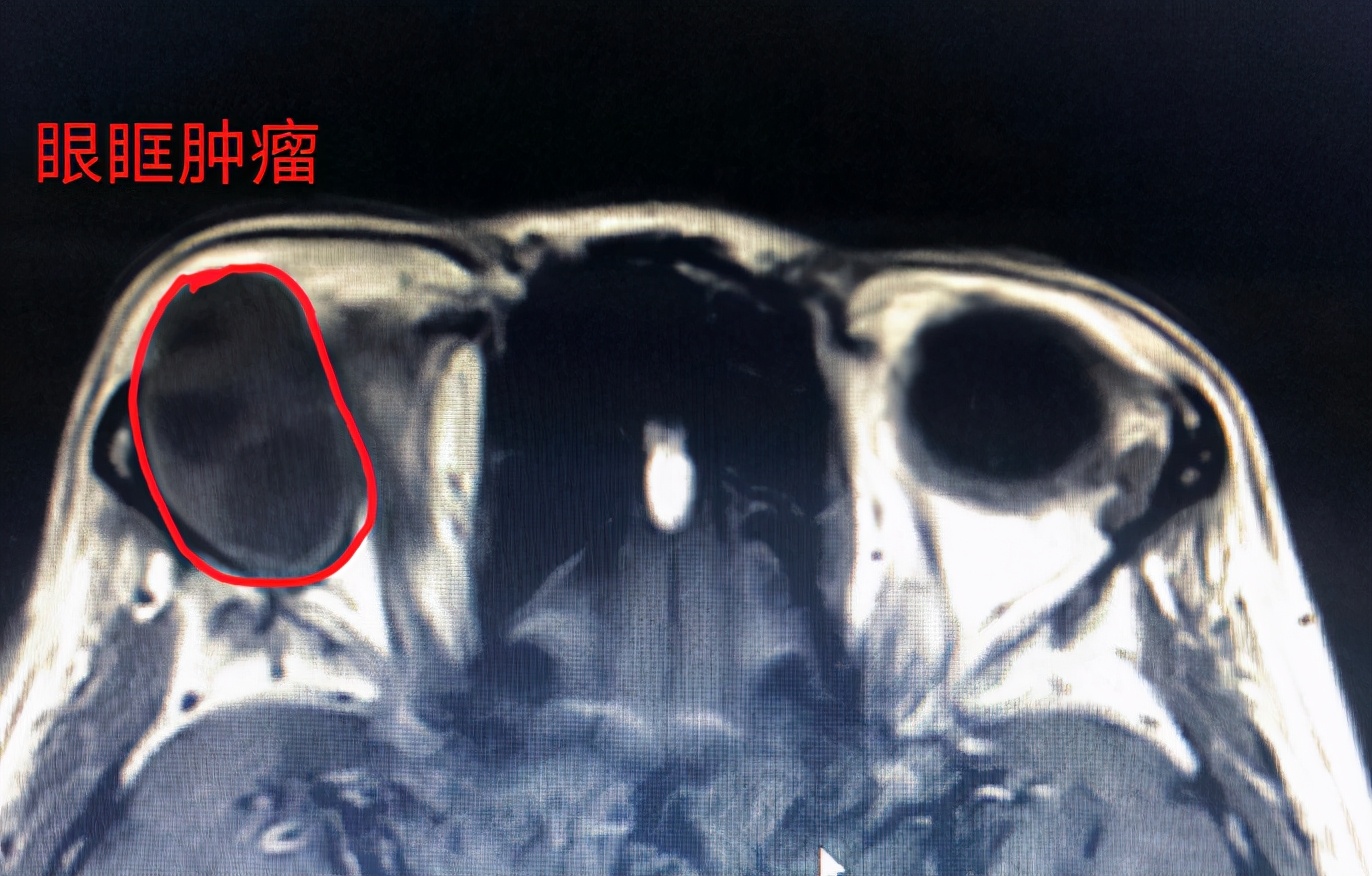

家住后湖的赵女士今年56岁,两年前就发现自己的右眼有点浮肿,但她以为是年纪大了有了眼袋。因为平时不疼不痒的,自己的视力也正常,就没放在心上。直到前段时间,她发现“眼袋”越来越严重,遮挡了大部分视野,家人提醒她两只眼睛不对称,这才引起重视,赶紧到家附近的武汉市中心医院后湖院区就诊。眼科医生接诊后,发现她眼睛浮肿并非眼袋,右眼明显向外突出,判断可能是眼眶肿瘤。进一步眼眶核磁共振检查发现,赵女士眼眶里有一个3厘米的占位,比眼球还大,(正常成年人的眼球前后径约24mm)。如果任其发展,随着肿瘤的继续增大,会压迫到视神经,甚至造成失明。

由于肿物体积较大,且位于眼球后上方,肿物影像显示内部信号不均匀,手术风险很大,如果术中稍微不慎损伤了旁边的视神经或者球后的主要血管,还会影响今后的视力。经过周密的术前准备,眼科副主任医师姚骏为赵女士实施了右眼开眶摘除手术,小心翼翼地完整摘除了肿瘤。术后,赵女士外突的右眼球重新回到原位,视力和眼球运动未受到影响。病检结果显示为malt恶性淋巴瘤,后续还需定期复查,必要时辅以放疗及化疗。